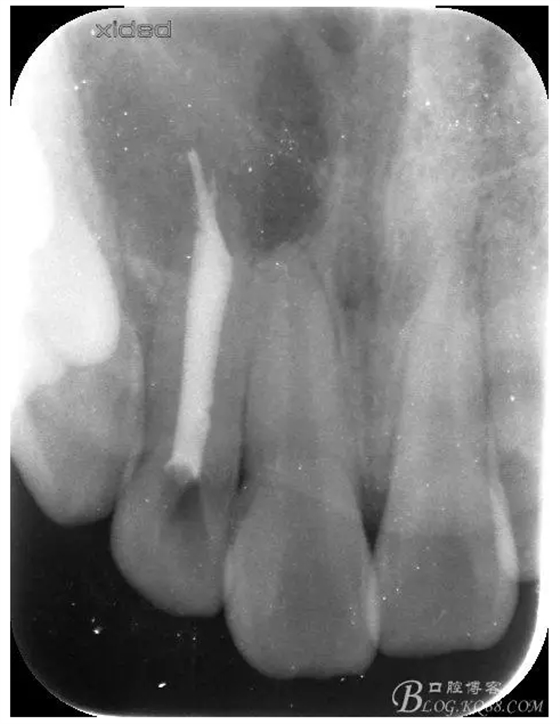

1.術(shù)前的根尖片檢查及根管治療影像:

圖7.切除根尖3mm的影像

圖8.根尖區(qū)超聲倒預(yù)備3mm